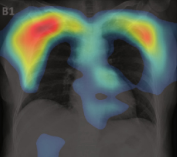

The second example, in Figure 5b) shows that the model does not take the lesions into account. The model states that parts of the lungs other than the ones marked by the radiologist are relevant for model prediction. Explanations that “roughly indicate the infection location” [32] are not acceptable for the robust model. The model should do this with the accuracy of the pixel marked by radiologists as relevant.